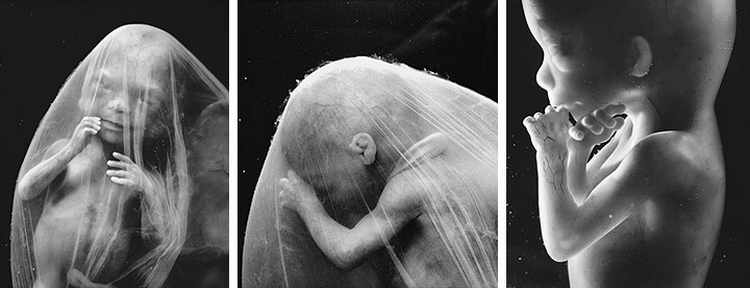

16-17 недель беременности: развитие малыша